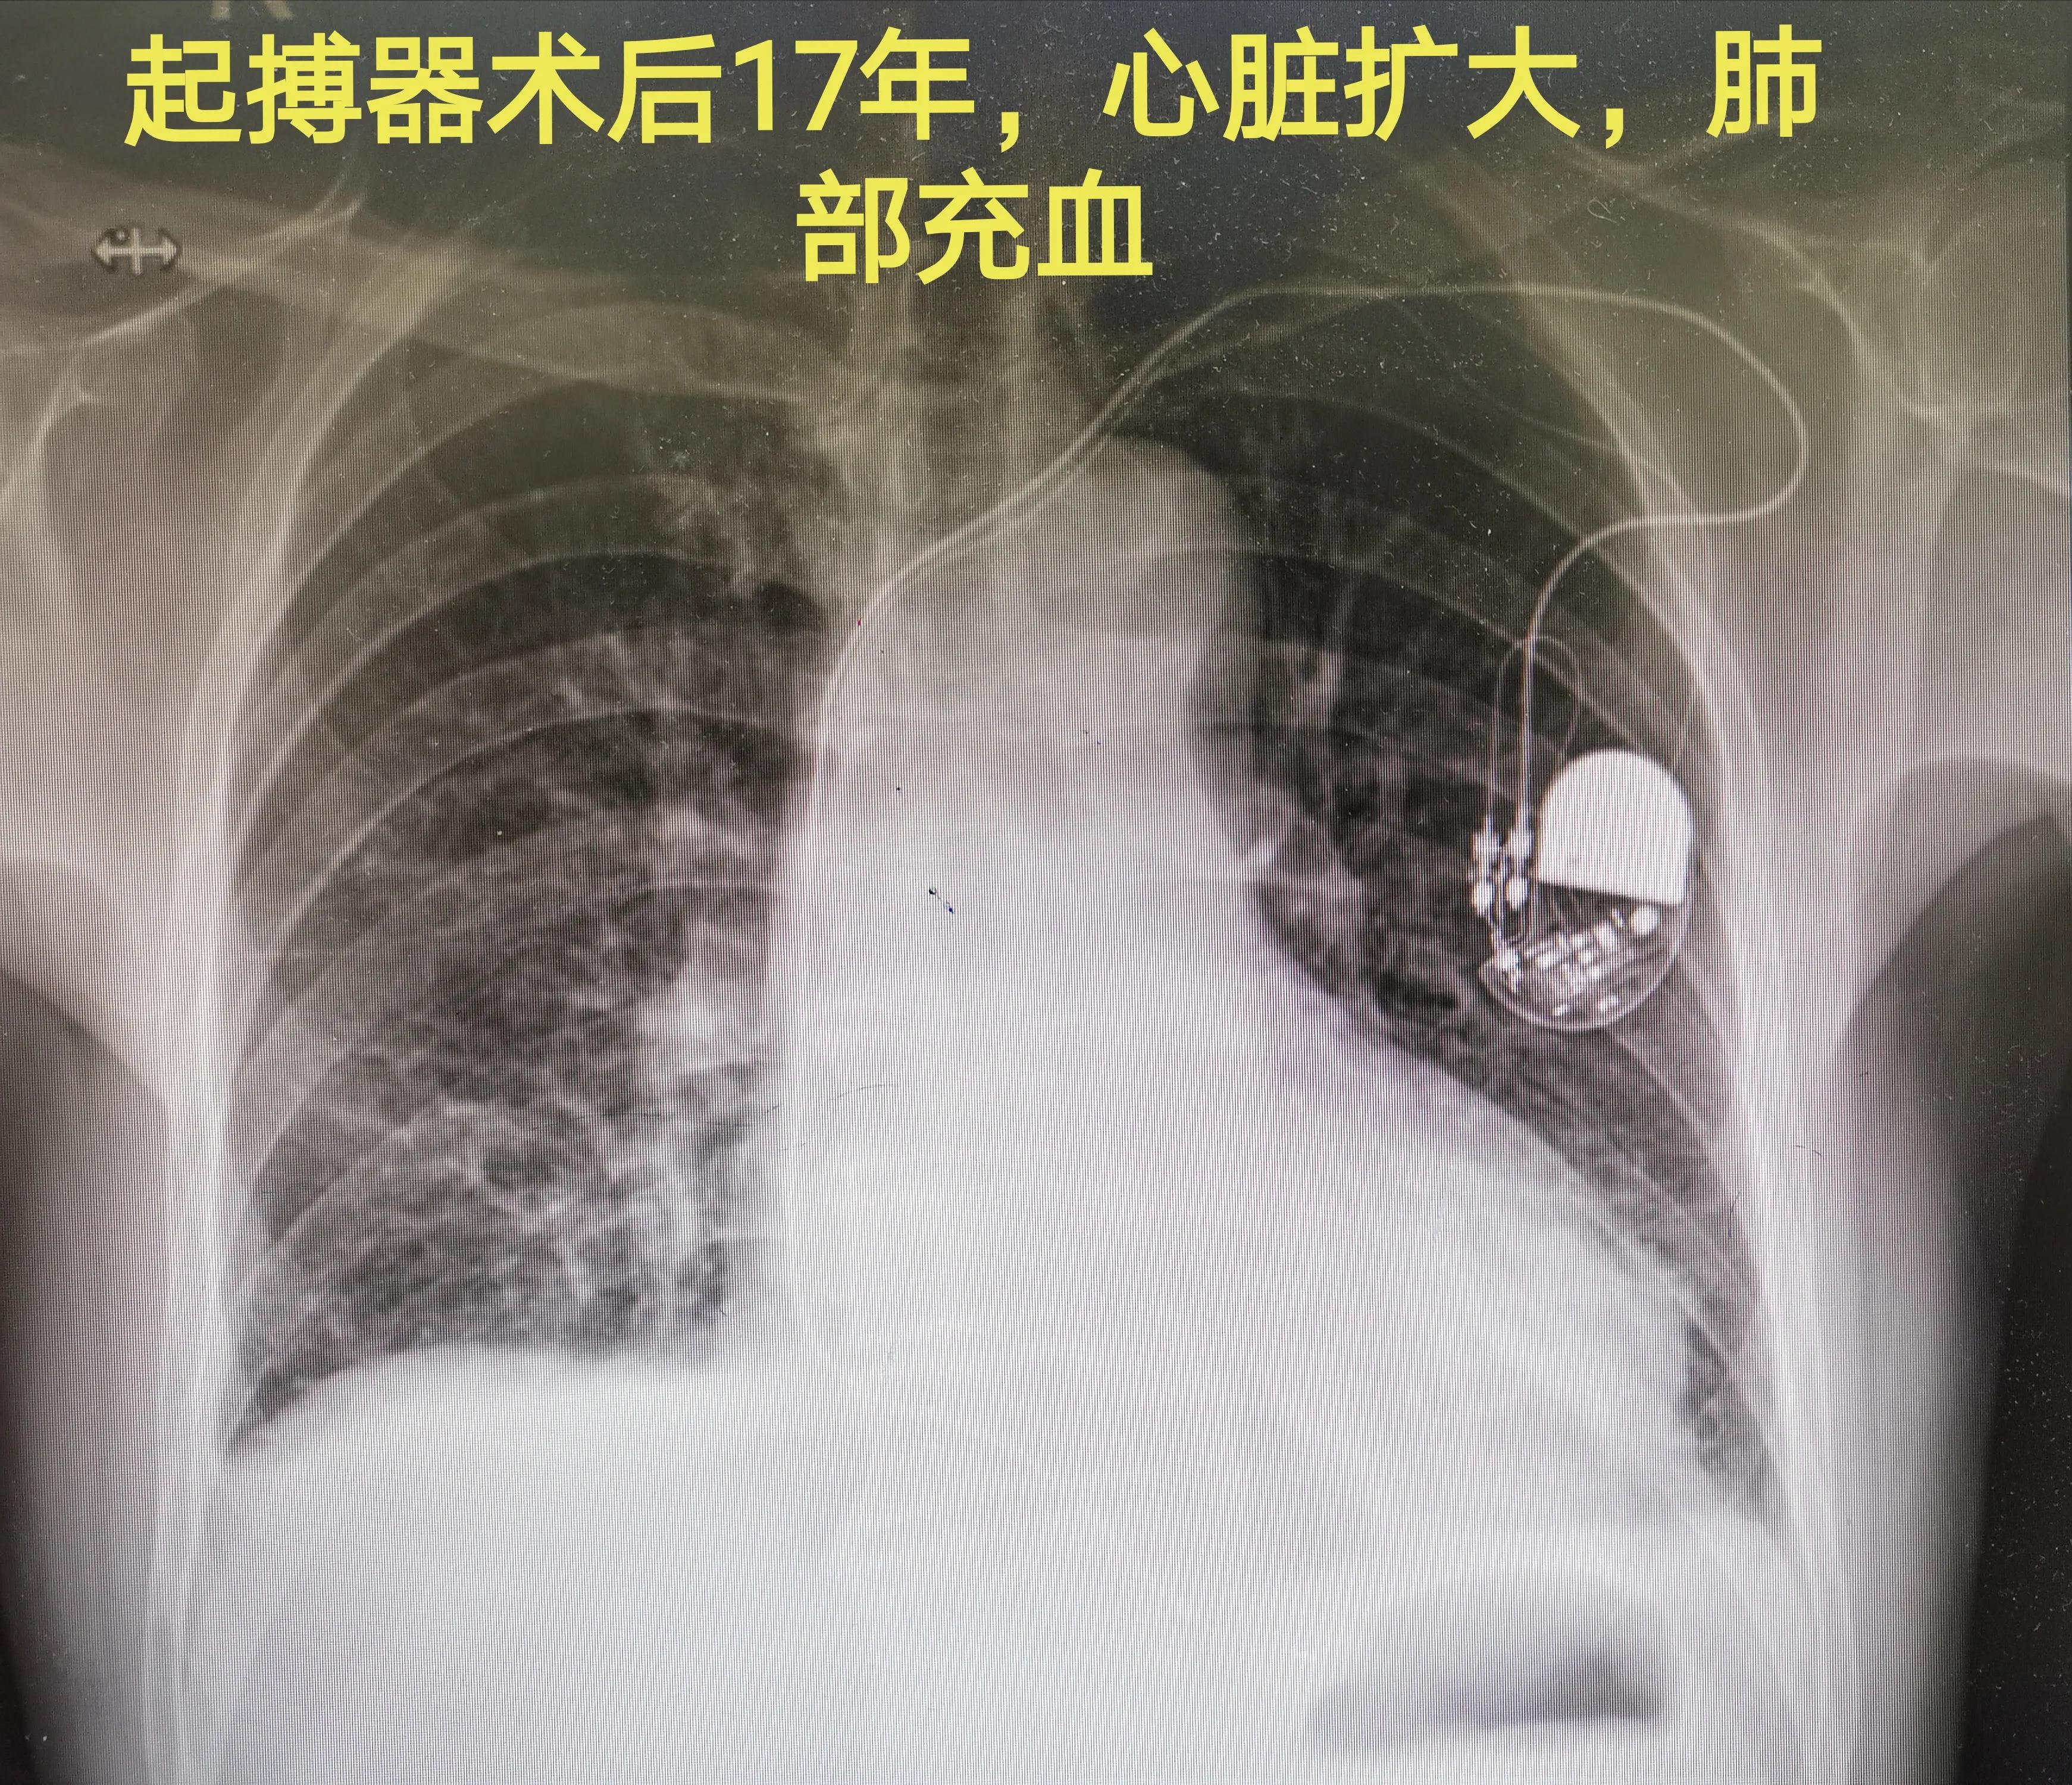

再放一张胸片,双腔起搏器,单极导线,右心耳-右室心尖部起搏导线,左心明显扩大,肺充血改变,同时发现起搏器囊带下移。